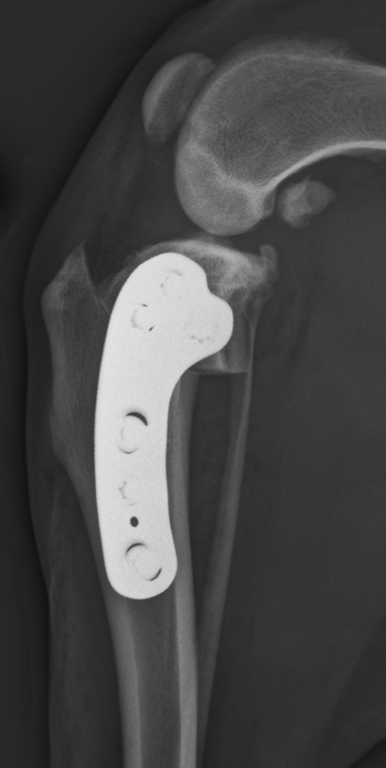

Hamilton Specialist Referrals Guarantees TPLO Surgeries

State-of-the-art veterinary hospital, Hamilton Specialist Referrals (HSR), is guaranteeing all tibial plateau levelling osteotomies (TPLO) for one year post-operatively from the beginning of March. This industry-leading move reflects the level of expertise on offer from the team of four RCVS and European orthopaedics specialists at Hamilton Referrals, in High Wycombe. The hospital’s latest expansion welcomed Dr Andy Craig, Diplomate of the European College of Veterinary Surgeons ECVS and an RCVS Specialist in Small Animal Surgery, further strengthening the renowned orthopaedics service which has recently performed their 1000th TPLO.

Managing Director, Clare Hamilton, explains: “TPLOs are one of a handful of surgeries where outcome is reasonably predictable given the right process takes place in terms of assessment, surgical protocols and rehabilitation. We feel we have ticked all those boxes and we are very confident of our surgical outcomes based on our track record of over 1000 TPLO procedures. Therefore, we are prepared to meet all costs in the unlikely event of a surgical breakdown, giving owners and referring vets that extra peace of mind when they entrust their pets to us.”

Hamilton Specialist Referrals recently doubled their hospital premises, and has increased their caseload, while reducing waiting times for appointments. This is relieving pressure on referring vets and providing reassurance for pet owners. The orthopaedics service is now able to offer all patients TPLO surgery within two weeks of a referral being requested.